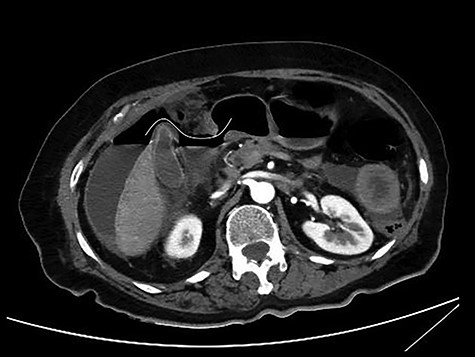

The patient was afebrile but hemodynamically unstable, with 115 bpm and a systolic pressure of 80 mmHg on presentation. Clinical examination revealed abdominal distension, diminished bowel sounds and severe tenderness with peritoneal signs in all of the abdominal quadrants. Her laboratory blood examination showed elevated number of neutrophils (7.77 K/μl), elevated C-reactive protein value (82.46 mg/dl) and decreased Na+ (119 mEq/l). After initial resuscitation, a computed tomography (CT) scan was performed. It showed free abdominal air and fluid in the peritoneal cavity, indicating an intestinal perforation (Figs 1–3).

CT scan without intravenous (iv) and oral (per os) contrast media administration: The disruption of lumen continuity at the level of duodenum bulb with presence of fluid (arrow head) and free air (arrows). There are also presence of free fluid in subdiaphragmatic space (dot) and edema in jejunum wall (open arrow). Contracted gallbladder is noted by star.